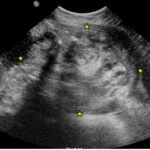

The CT scan with oral contrast in the emergency department revealed a large heterogeneous abdominopelvic mass measuring 13.2 x 18.8 x 23.1 cm (see white lines), suggestive of an ovarian teratoma from the right ovary. This mass included fat, fluid, calcifications (see yellow arrows), and enhancing soft tissue components. The teratoma resulted in mass effect upon large and small bowel loops (see blue highlighted areas), inferior vena cava (IVC), distal aorta (see red highlighted area) and right common iliac artery. A small volume of ascites was also observed. There was no evidence of bowel obstruction, vascular occlusion or other significant emergent finding. Additionally, transabdominal and transvaginal ultrasound images were obtained. The transabdominal image visualized the abdominopelvic mass (see four yellow stars). The transvaginal image visualized a cross section of the teratoma (see four red stars) in relation to the bladder (see four blue stars).